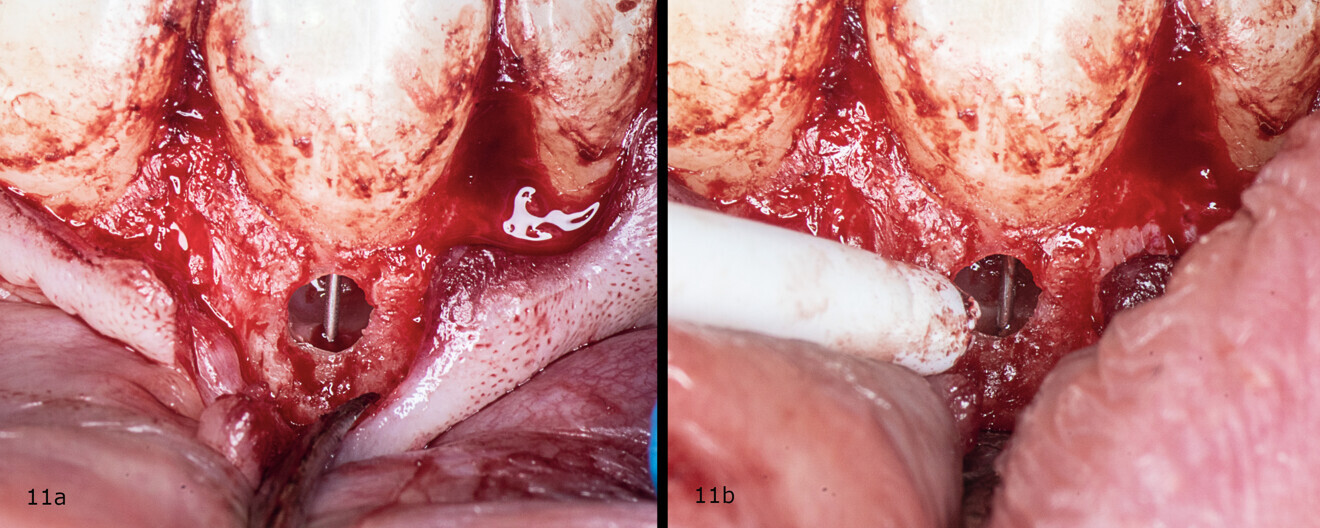

Figs. 11a & b: Irrigation of the root canal.

An incision was made from the maxillary left central incisor through the gingival sulcus to the right maxillary canine. After raising a flap, the granulation tissue was removed from the resorption cavity with a small excavator (Figs. 9–11). The root canal shaping protocol was performed with conventional chemomechanical preparation. The shaping sequence began with negotiation with passive hand files, followed by preparation with rotary files and irrigation using sodium hypochlorite with manual needle agitation. The irrigation protocol was performed as described in Case 1.